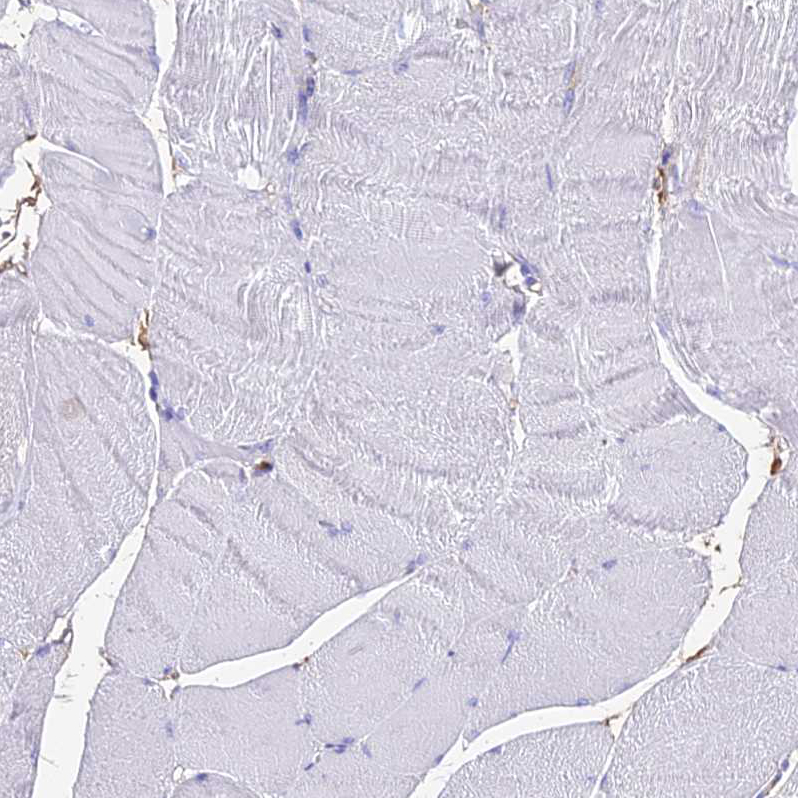

Immunohistochemical staining of human fallopian tube shows strong positivity in cilia of glandular cells.